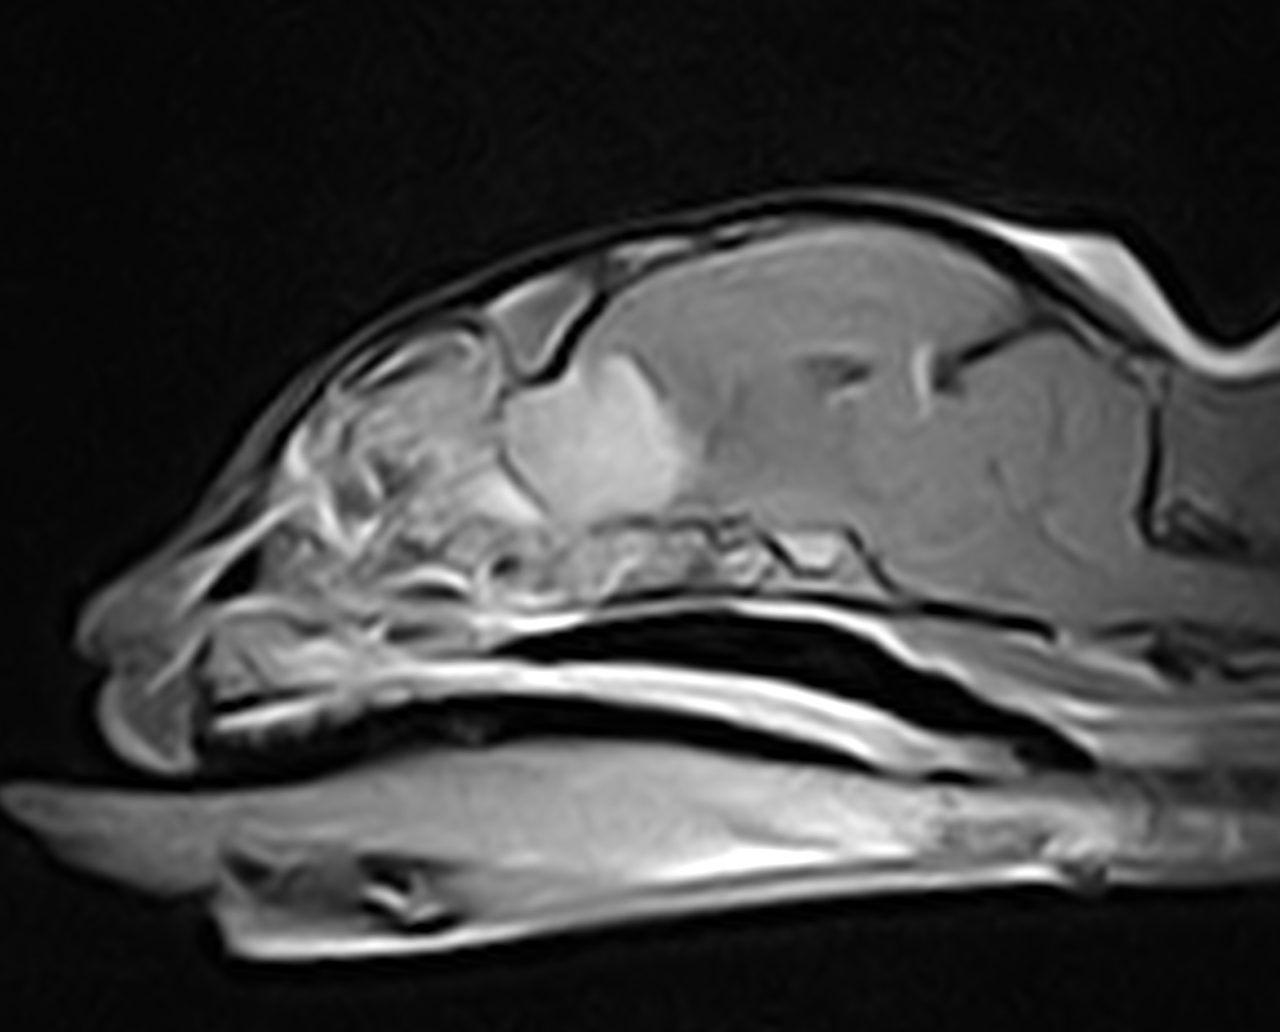

12歳の猫が2週間前よりふらつき、食欲不振、硬直性の痙攣があるとのことで、主治医から紹介がありました。MRIでは前頭葉を中心としたMASSエフェクトを伴う病変が確認されました。リンパ腫あるいは髄膜腫が強く疑われました。CSFでは無色透明で髄液蛋白60mg/dl、Ph8.5 細胞数2(5以下正常)単核球100%パンディ反応(+1)。CSF中のGlu63mg/dl、CK<10、Na 166 K 2.9 Cl 131。手術までの1週間の間にステロイドを中心とした内科療法を実施したところ、臨床症状も改善し、再度、実施したMRIでも以前の病変がほぼ消失していました。ステロイドに強く反応したことからリンパ腫の存在が強く疑われました。今後、化学療法を継続するか?否か?あるいはFIPなどの鑑別を行うために、嗅球と前頭葉の生検が行われました。生検の結果、コロナウイルスの感染、リンパ腫の存在は否定されました。また、血清学的にもトキソプラズマ、FIPの関与は否定的でした。そのため、プレドニゾロンを継続し、経過観察中です。2017年に猫のMUOについて世界で初めてイギリスより16例のまとまった報告が初めての論文として掲載されており、今回の患者さんはそのFMUOのカテゴリーに分類されると考えられました。